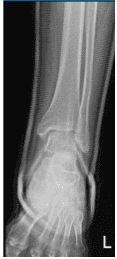

The patient presented an Xray result and shown status post external application of a cast for mildly displaced oblique fracture of the distal fibula.

Left Ankle X-Ray complete 3 or more views